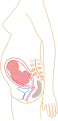

De acuerdo a su desarrollo, el embarazo se suele dividir en tres etapas de tres meses cada una, con el objetivo de simplificar la referencia a los diferentes estados de desarrollo del feto.

Durante el primer trimestre el riesgo de aborto es mayor (muerte natural del embrión o feto). Esto tiene mayor incidencia en embarazos conseguidos mediante fecundación in vitro, ya que el embrión implantado podría dejar de desarrollarse por fallos en los cromosomas heredados de los gametos de sus progenitores.

Mes 1: Mide 4 mm y pesa 1 g. Desarrollo incipiente de la cabeza. El corazón ya late

Mes 1: Mide 4 mm y pesa 1 g. Desarrollo incipiente de la cabeza. El corazón ya late Mes 2: Mide 3 cm y pesa 3 g. Desarrollo de brazos y piernas, así como del cerebro y órganos internos.